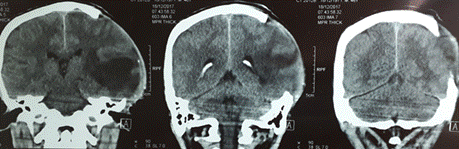

En las figuras 1, 2 y 3 se presentan neuroimágenes realizadas al paciente. (Figura 1)(Figura 2)(Figura 3)

Figura 1 Resultados de la tomografía axial computarizada en vista posterior, en la cual se puede observar la inflamación en el hemisferio izquierdo del paciente.